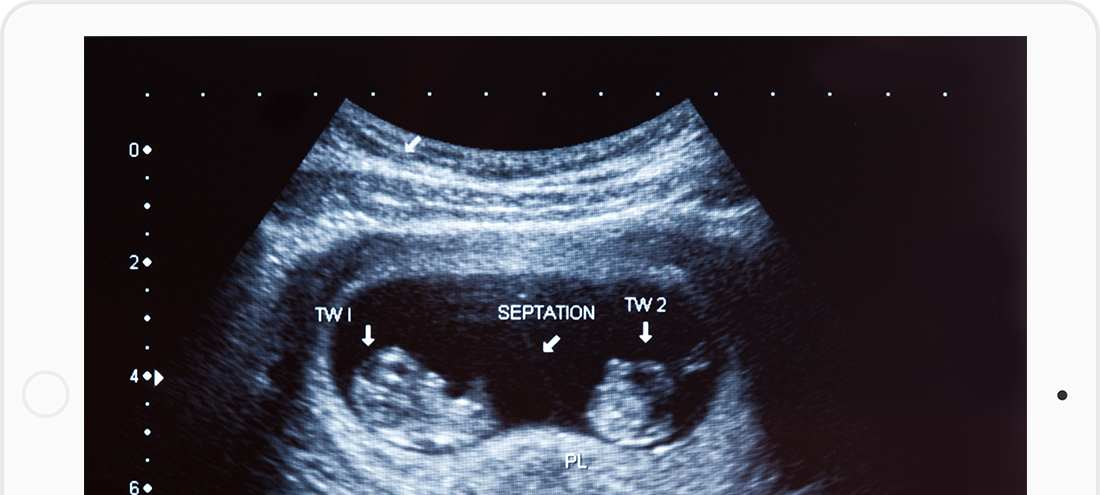

Determine gestational age and expected due dateCheck for multiple pregnancies (twins or triplets)Identify early complications such as ectopic pregnancy or risk of miscarriage